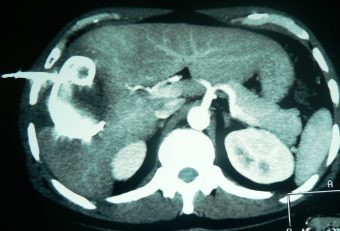

Drenaje percutáneo de absceso hepático

Envíado por Dr. Carlos Miguel Zavaleta Consuegra